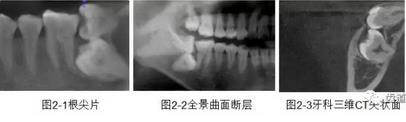

一)牙體牙髓病科

CBCT在牙體牙髓病科治療中,對牙根周圍的解剖關(guān)系、炎癥病變、囊腫等就能夠輕而易舉的進行診斷。甚至與牙齒內(nèi)根管的數(shù)目、走向、分支等都能夠通過牙科CT進行展示,使臨床醫(yī)生的根管治療不再是完全憑手感的“經(jīng)驗科學(xué)”。通過CBCT,還可以對一些“久治不愈“的疑難病例進行檢查和診斷,例如根縱列的診斷、根管內(nèi)異物的定位等,找準(zhǔn)了原因,結(jié)合先進的治療技術(shù)因病施治,使疑難病例的治療變的輕松起來。

1、牙髓根管治療

1)根管治療中牙膠尖充填在CBCT中的影像

2)根管測量